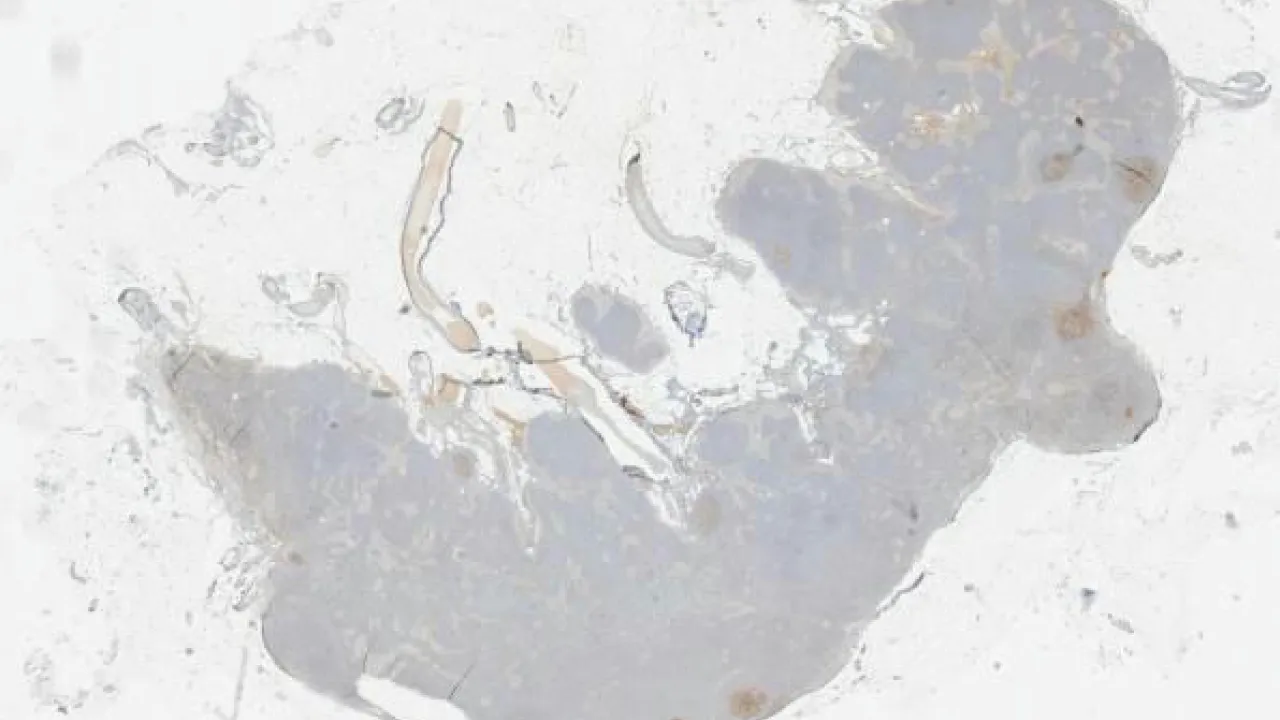

Bone Marrow, Acute myeloid leukemia, CD34 stain